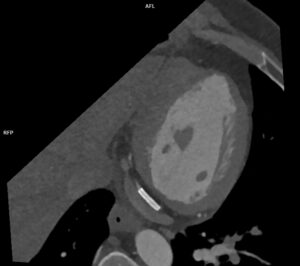

Figurile 6 si 7: reconstrucție multiplanară din examinarea inițială cu evidențierea stenozei severe de la nivelul arterei circumflexe, ce a fost stentată ulterior

Figurile 9 si 10: reconstrucție multiplanară din examinarea recentă cu evidențierea stentului permeabil de la nivelul arterei circumflexe